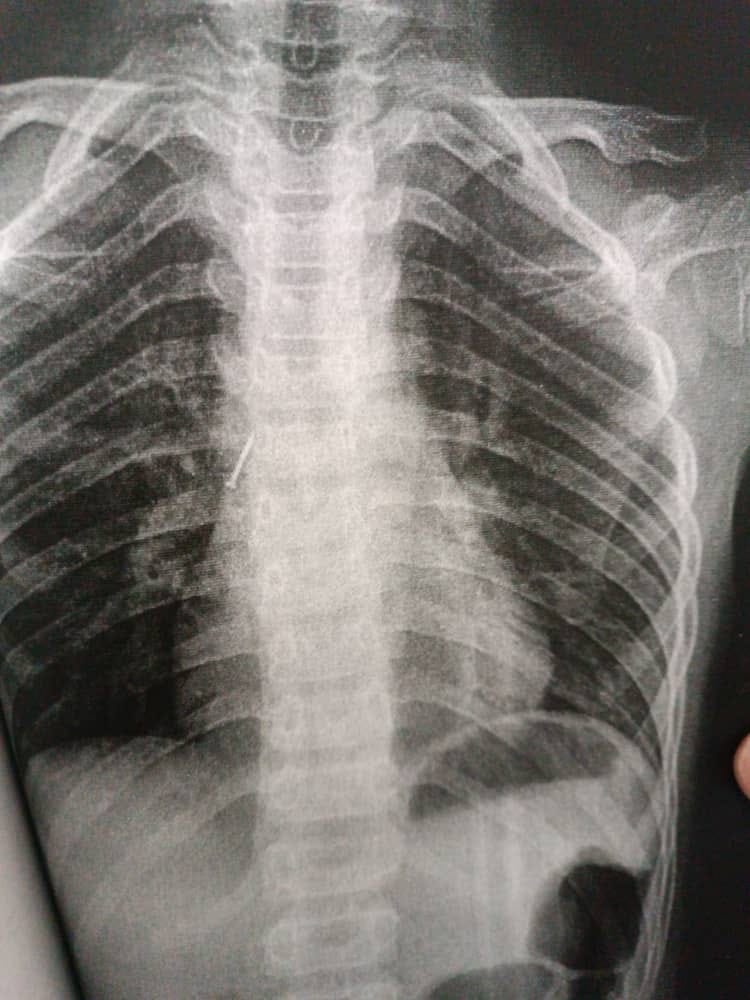

Бишкек, 08.08.23. /Кабар/. Кечээ, 7-августта Ош облустар аралык балдар клиникалык ооруканасына учтуу зат жутуп алган 10 жаштагы бала түшкөн. Бул тууралуу оорукананын басма сөз кызматынан билдиришти.

Маалыматка ылайык, бала оң өпкөсүнөн жабыркап, канцелярдык мык бронхага сайылып калган. Дарыгерлер тарабынан оор абалдагы балага тезинен жардам көрсөтүлүп, бала аман калды.